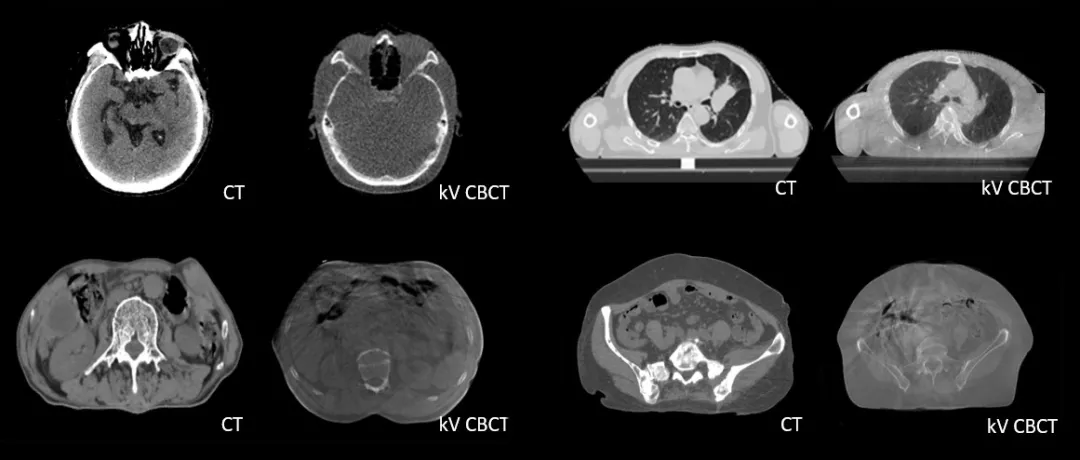

診斷級(jí) CT對(duì)比kV-CBCT影像,更好地顯示器官和軟組織的邊界和細(xì)節(jié)